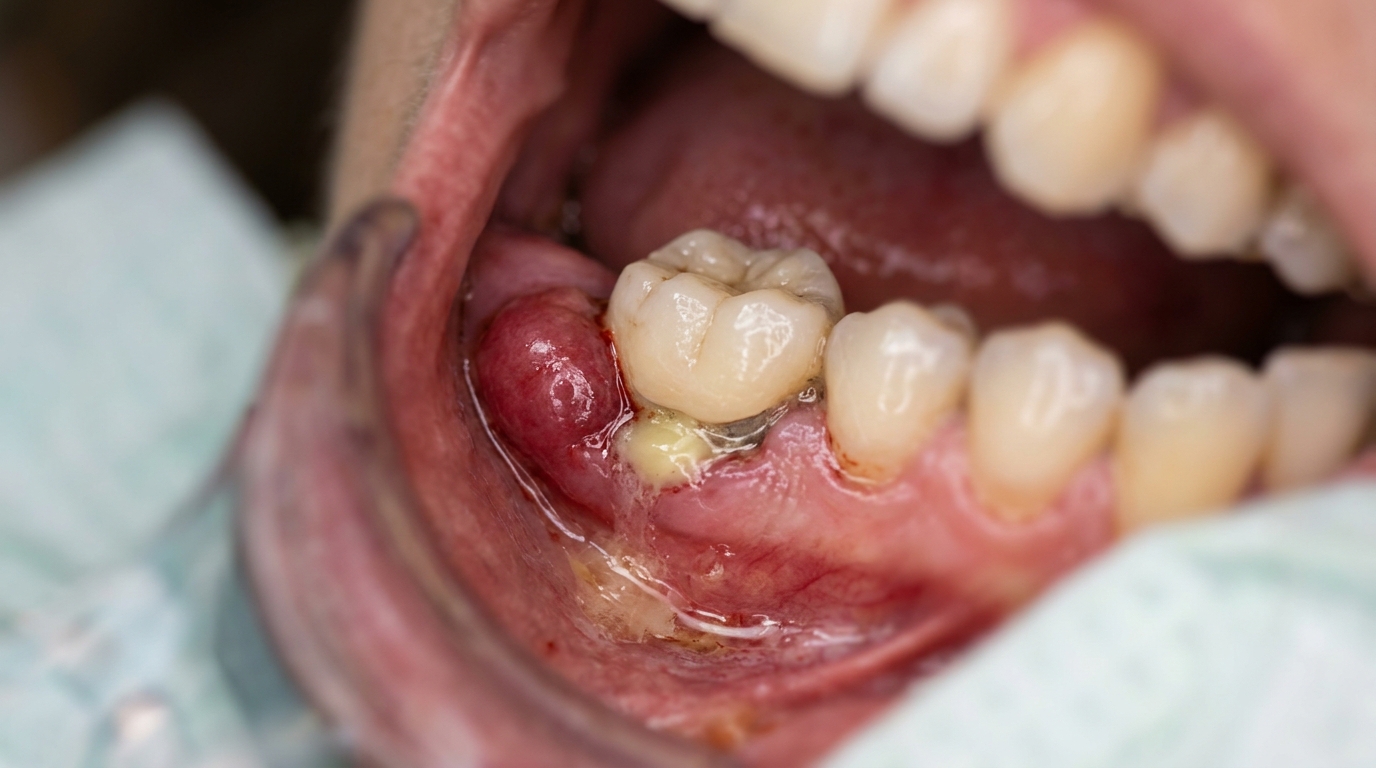

Один из первых спутников — боль или дискомфорт в области протеза. Если зуб под коронкой ноет пристучании или реагирует на холодное/горячее, это указывает на воспаление пульпы или трещину. Десна вокруг коронки может отекать, кровоточить или менять цвет на ярко-красный. В запущенных случаях появляется гнойное выделение, усиливающий запах до уровня, заметного окружающим.

Визуальные изменения тоже важны. Темные пятна на десне или потемнение самого зуба под коронкой сигнализируют о некрозе тканей. Если коронка расшаталась, вы можете заметить просвет между ней и десной. Для самодиагностики полезно использовать зеркало и фонарик: осмотрите зону на наличие налета желтого или зеленоватого оттенка — признака бактериальной активности.

Фото симптомов: отек десны, гнойное выделение и расшатанная коронка на зубе.